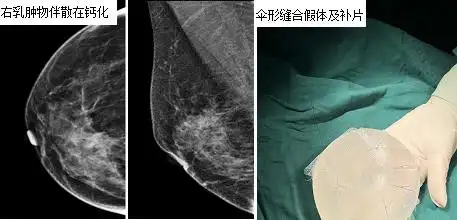

患者,女,52岁,发现右乳肿块2月来诊.

皮肤可见卫星灶,行改良根治术,完整切除了原发肿块及卫星结节

乳房皮肤形成散在分布的质硬结节,即所谓"皮肤卫星结节".